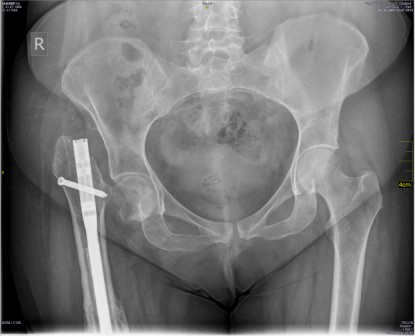

Пациентка В,30 лет. Травма 09.01.2014 в результате падения с высоты 5

этажа, в ЛПУ был поставлен диагноз: открытый перелом правого бедра и Th

11-12 позвонков. Пациентка госпитализирована в травматологическое

отделение, за бугристость большеберцовой кости было наложено скелетное

вытяжение в течение, выполнена ПХО раны с\3 правого бедра. Через 2

месяца после заживления раны бедра, скелетное вытяжение было снято,

04.03.2014 выполнена операция закрытого интрамедуллярного синтеза

правого бедра. В апреле 2014 года была выписана на амбулаторное лечение,

в мае 2014 начала ходить с частичной нагрузкой на правую ногу. 26 января

2015 года при повторной рентгенографии выявлен несросшийся перелом

правой бедренной кости, была направлена в наш институт травматологии с

диагнозом : Посттравматическая деформация правого бедра на фоне

несросшегося перелома средней трети диафиза правого бедра после

остеосинтеза интрамедуллярным стержнем. Псевдоартроз шейки правой

бедренной кости, сопутствующие заболевания: Болезнь Иценко-Кушинга,

ремиссия. Симптоматический сахарный диабет, инсулинопотребность.

Диабетическая Нефропатия, ХПН0. Диабетическая сенсо-моторная

полинейропатия нижних конечностей. Неправильно сросшиеся переломы тел

ThXI-XII позвонков.

18.03.2015 Выполнен реостеосинтез правого бедра интрамедуллярным

стержнем с антибактериальным покрытием со статическим блокированием. На

3-и сутки после операции пациентка была активизирована: начала ходить с

помощью костылей с частичной нагрузкой на правую ногу. На повторном

приеме через 3,5 месяца после операции установлен диагноз: сросшийся

перелом правой бедренной кости после остеосинтеза интрамедуллярным

стержнем, псевдоартроз шейки правой бедренной кости.

Можно ли предложить данной молодой пациентке что-то, кроме

эндопротезирования т/б. И если вы думаете, что нет, то какая тактику

будет дальше : вначале удалить стержень а потом выполнить

эндопротезирование или выполнить их удаление стержня и протезирование в

одну операционную сессию. Спасибо вам за ваши мнения !

Имя     : VAGNER I-V- - 31-07-1985- CR from 03-07-2015 S0 I0.JPG